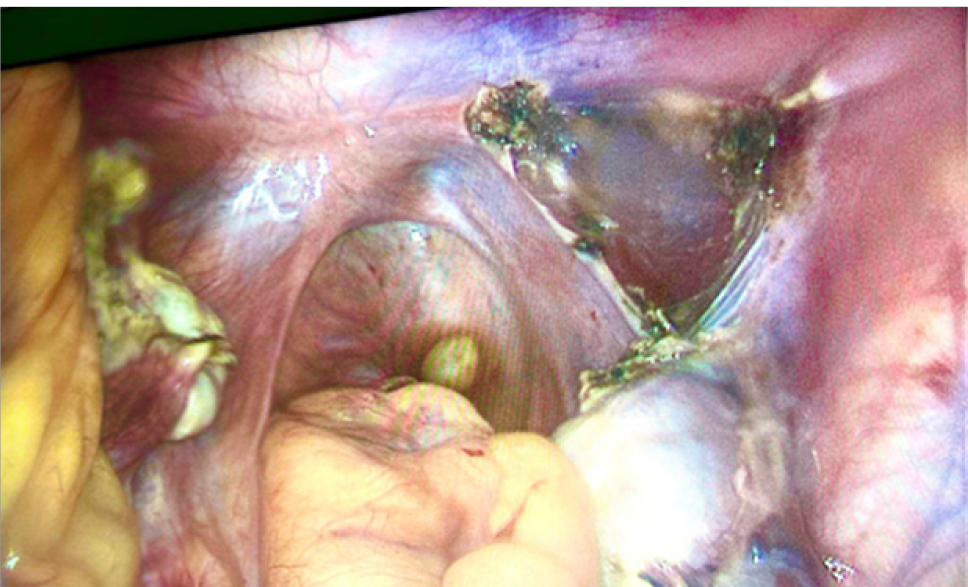

В связи с наличием объемного образования малого таза больших размеров, 11.10.2022 г. после полного лабораторного и клинического обследования, в плановом порядке выполнена лапароскопия. Интраоперационно обнаружено: матка представлена рудиментом – соединительно-тканным тяжом, из которого вправо исходит округлое образование около 8 см в диаметре – миоматозный узел (рис. 1). Правая маточная труба отходит от латерального полюса миоматозного узла, не изменена, с выраженными фимбриями. Влево от соединительно-тканного тяжа исходит рудиментарный мышечный рог матки с маточной трубой (без особенностей). Яичники с обеих сторон обычного строения, нормальных размеров. В связи с обнаруженным была выполнена миомэктомия, билатеральная тубэктомия. Миоматозный узел с маточными трубами извлечены из брюшной полости в стерильном контейнере (рис. 2).